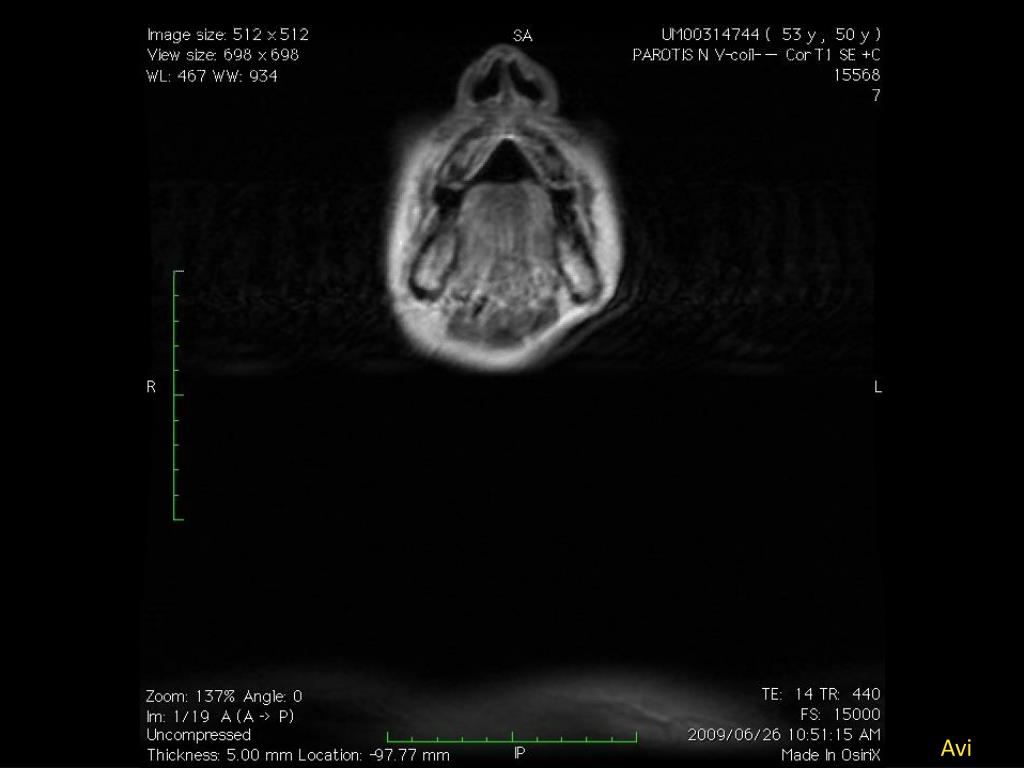

23. Adult with neck mass • 53 yr • Right neck mass

24. Avi

25. Avi